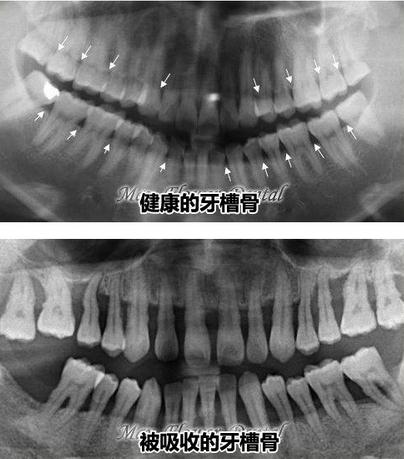

牙槽骨吸收是牙周炎的一个主要病理变化,一般只要拍一张全景片,就能看出牙槽骨吸收的方式、骨量的多少。平常不注意刷牙动作,使用了过硬牙刷、牙膏中摩擦剂颗粒过粗等,对牙龈也有相对的伤害。